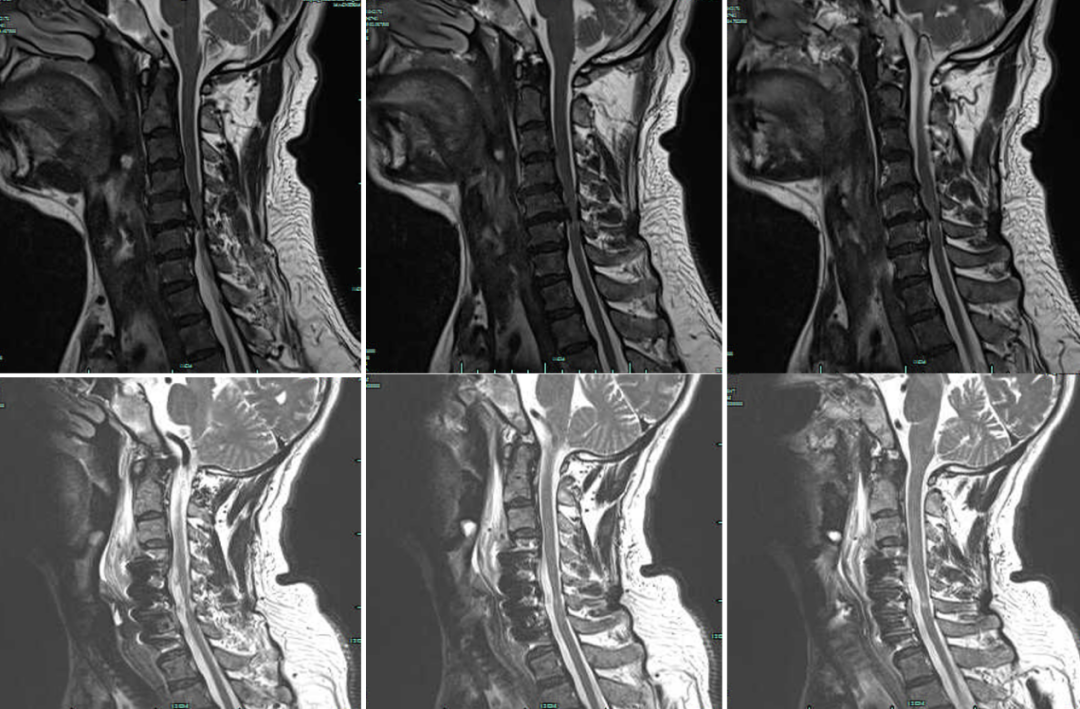

术前术后X线:

术前术后MRI: